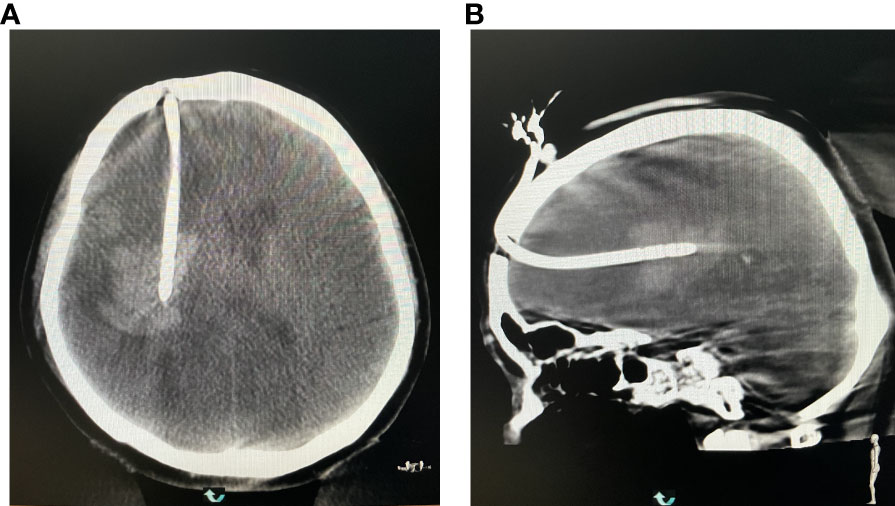

2.4.4 Rechecking the position of the drainage tube

The DSA machine was used for CT scanning, collecting data, and transmitting the information to a computer. It was ensured that the drainage tube was located at the center of the hematoma (Figure 9).

Figure 9 (A) Reexamining the puncture results in the coronal position. (B) Rechecking the puncture results at the axial position.